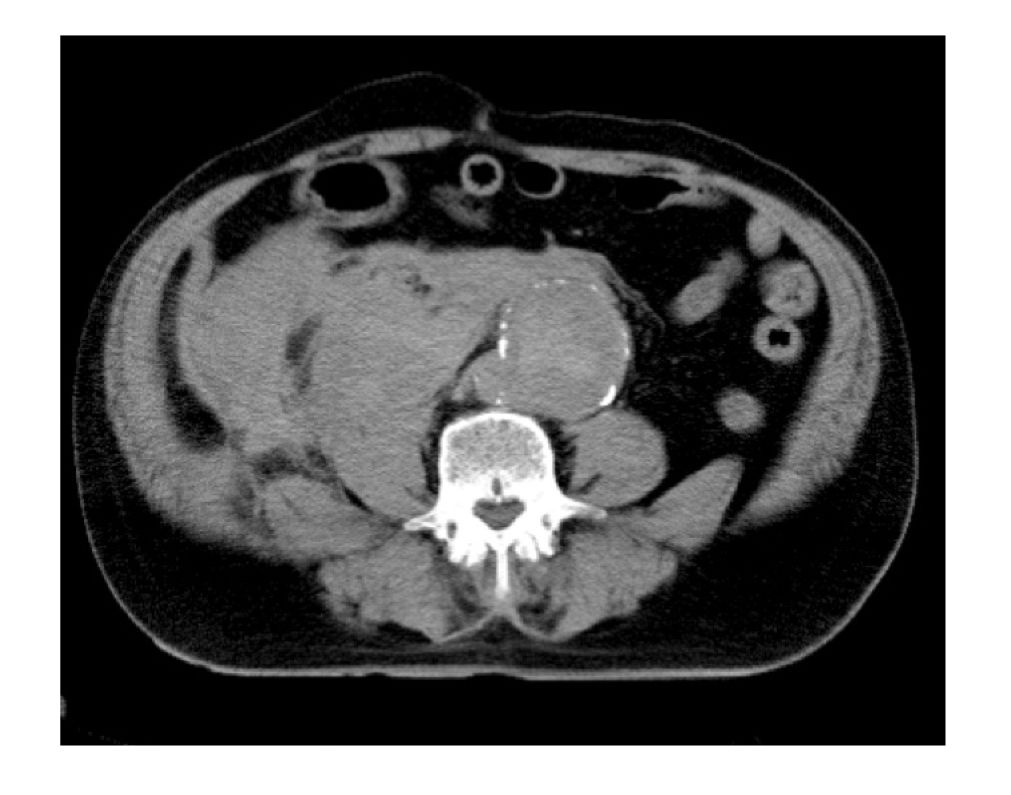

日々の症例 174 腹部大動脈瘤破裂